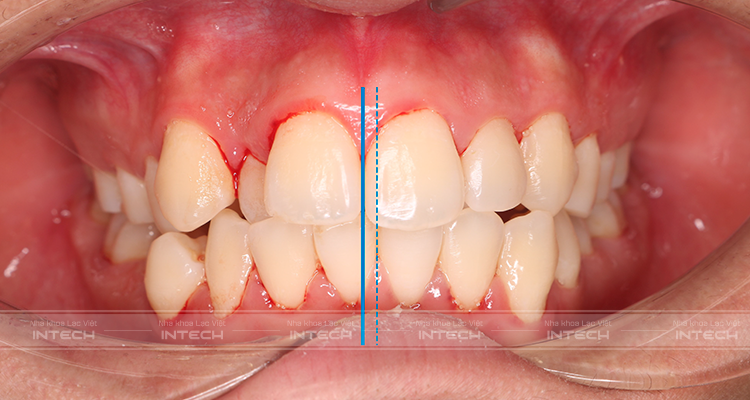

- Chen chúc khấp khểnh cả hai hàm ở mức độ trung bình

- Răng cửa hàm trên bên trái bị mọc kẹt vào trong làm cho toàn bộ hàm trên bên trái bị xô sang bên phải khiến đường giữa hàm trên và hàm dưới bị lệch

Phần hàm trên bên trái có răng cửa có hình thể bất thường.

Đường giữa hai hàm răng lệch

Răng cửa hàm trên mọc kẹt

Hàm răng kém thẩm mỹ của bạn Trần Đức Khải